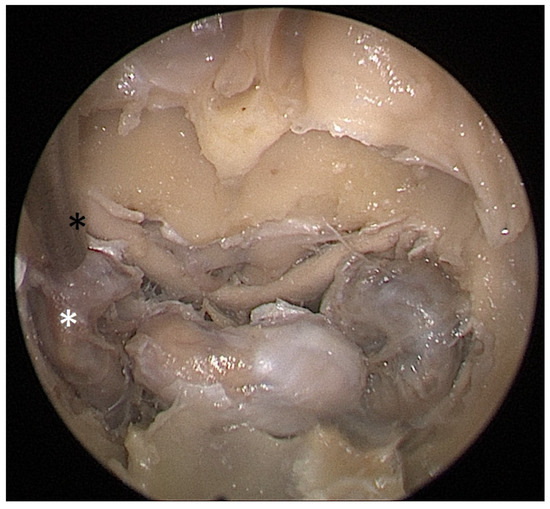

Cadaver pituitary surgery: On each of the two cadaveric heads, we used the paraseptal binostril approach for the sphenoid sinus. A 30° Storz endoscope (Karl-Storz, Austria, Vienna) was used. The head was mounted in a Mayfield cranial stabilization device. The surgery started with a lateralization of the inferior and medial turbinates. The anterior sphenoid wall and ostium to sphenoid sinus were identified. Using the straight suction with a marked scale, 1 cm and 2 cm distances from the anterior sphenoid wall were measured and marked with a scalpel on the posterior part of the septum. Using a scalpel, Kerrison punch, and backbiter punch, a posterior septal resection 1 cm from the anterior wall of the sphenoid was performed. We continued with the wide opening of the sphenoid cavity and resection of the intersphenoidal septum and the full exposure of the posterior wall, both ICAs, and optocarotic recesses (OCR). The posterior wall of the sphenoid sinus and dura were resected to better identify anatomic landmarks, with both ICAs, pituitary gland, chiasma, and optic nerves visible at the end of a resection (Figure 4). The straight suction was inserted into the sphenoid sinus so that the instrument’s tip was in the most lateral position in the sphenoid sinus without infracturing the rest of the nasal septum. A picture was taken in this position to evaluate the most lateral part of the sphenoid sinus that could be reached with a straight instrument with a 1 cm septal resection without infracturing the nasal septum (Figure 5). Enlargement of the septal resection to 2 cm from the anterior sphenoid wall was performed with a backbiter punch and scalpel. The straight suction was inserted into the sphenoid sinus so that the instrument’s tip was in the most lateral position in the sphenoid sinus without infracturing the rest of the nasal septum. A picture was taken in this position to evaluate the most lateral part of the sphenoid sinus that could be reached with a straight instrument, with a 2 cm septal resection, without infracturing the nasal septum (Figure 6).

Each head was operated on twice. First, a binostril approach and a 1 cm posterior septal resection were performed. This allowed us, in both cadavers, to comfortably reach the medial part of the carotids bilaterally with straight suction. This resection size would be sufficient for a safe tumor extraction in non-extended tumors. Then, a 2 cm extension of the septal resection was performed. A more extensive resection allowed us to reach the lateral margin of the ICA bilaterally. It also gave us better maneuverability and an overview of the operated area.

Figure 5. Opened sphenoidal sinus, endoscopic view, straight suction (black asterisk) reaching the medial border of ICA (white asterisk) with a 1 cm septal resection.